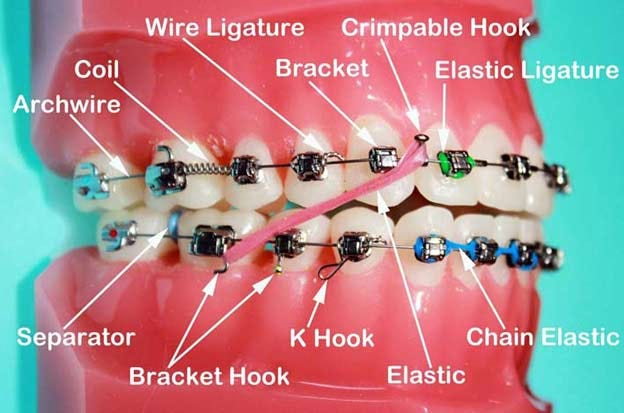

矯正牙套是透過長時間持續施加壓力在牙齒上,逐漸將牙齒推移到理想位置的裝置。這個過程需要好幾個部件協同運作:

- 每顆牙齒上黏著的小托槽作為固定點,

- 將這些托槽串連起來的弓形金屬線提供移動牙齒的力量方向,

- 有時還會加上橡皮筋來輔助施力、調整上下顎的對齊。